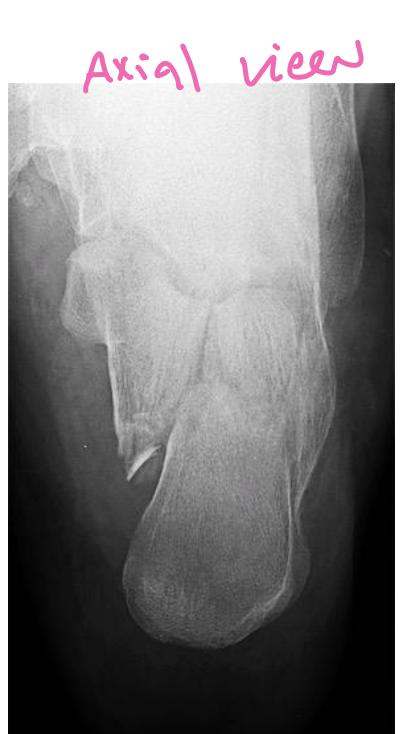

Calcaneal Fractures

Calcaneal Fracture

Complications: If displaced, can lead to osteoarthritis of subtalar joint which is painful Evaluation: CT scan to assess displacement Treatment: Conservative management

Calcaneal Fracture Evaluation

Q2: What other image you need for better evaluation of fracture?

- Calcaneal fracture

- CT scan to show the displacement